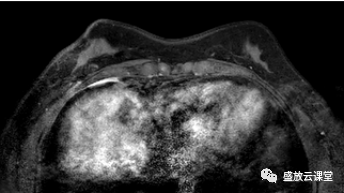

影像学表现

征象分析

特点归纳

诊断结果